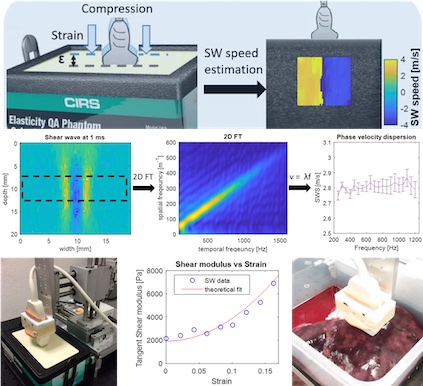

[2019] Corin F. Otesteanu, Bhaskara R. Chintada, Marga B. Rominger, Sergio J. Sanabria, and Orcun Goksel:

"Spectral Quantification of Nonlinear Elasticity using Acoustoelasticity and Shear-Wave Dispersion",

IEEE Trans Ultrasonics, Ferroelectrics, and Frequency Control 66(12):1845-1855, Aug 2019.

[2019] Corin F. Otesteanu, Bhaskara R. Chintada, Marga B. Rominger, Sergio J. Sanabria, and Orcun Goksel:

"Spectral Quantification of Nonlinear Elasticity using Acoustoelasticity and Shear-Wave Dispersion",

IEEE Trans Ultrasonics, Ferroelectrics, and Frequency Control 66(12):1845-1855, Aug 2019.

[2018] Corin F. Otesteanu, Sergio J. Sanabria, and Orcun Goksel:

"Robust Reconstruction of Elasticity Using Ultrasound Imaging and Multi-frequency Excitations",

IEEE Trans Medical Imaging 37(11):2502-2513, Nov 2018.

[2018] Corin F. Otesteanu, Sergio J. Sanabria, and Orcun Goksel:

"Robust Reconstruction of Elasticity Using Ultrasound Imaging and Multi-frequency Excitations",

IEEE Trans Medical Imaging 37(11):2502-2513, Nov 2018.

[2022] Bhaskara R. Chintada, Richard Rau, and Orcun Goksel:

"Nonlinear Characterization of Tissue Viscoelasticity with Acoustoelastic Attenuation of Shear-Waves",

IEEE Trans Ultrasonics, Ferroelectrics, and Frequency Control 69(1):38-53, Jan 2022.

[2022] Bhaskara R. Chintada, Richard Rau, and Orcun Goksel:

"Nonlinear Characterization of Tissue Viscoelasticity with Acoustoelastic Attenuation of Shear-Waves",

IEEE Trans Ultrasonics, Ferroelectrics, and Frequency Control 69(1):38-53, Jan 2022.